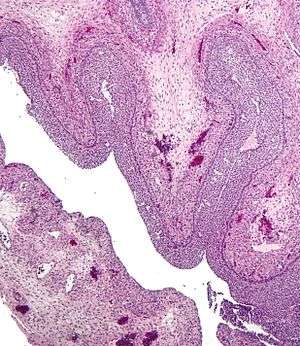

Luteinized follicular cyst. H&E stain.

- Corpus Luteum cyst: hemorrhage into persistent corpus luteum. Commonly regresses spontaneously.